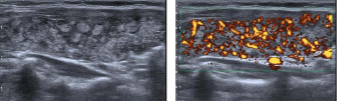

Which Doppler finding is characteristic of active Graves’ disease?

Thyroid inferno” pattern

This “thyroid inferno” appearance is most characteristic of:

Grave’s Disease